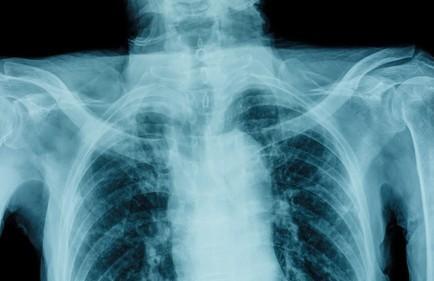

Possible Rib and Chest Injuries

While neck and back issues can certainly be causes for serious concern, the development of their related symptoms is rather unsurprising to most car crash victims. Chest pains, on the other hand, tend to raise many more questions as they are frequently associated with life-threatening cardiac conditions and episodes. Fortunately, after a motor vehicle accident, there may be several explanations for thoracic pain and discomfort.

Sturdy seatbelts and rapidly inflated airbags, without question, can reduce the likelihood of fatalities related to car accidents. That is not to imply, however, that their proper use completely prevents injury. In some cases, they may even contribute to injuries, particularly to the chest, ribs, and abdominal regions. Chest pains that develop hours or days after an accident are most commonly an indication of:

- Cracked or fractured ribs;

- Sternal fractures;

- Bruising to the ribs; and

- Soft tissue injuries and bruising.

Musculoskeletal injuries such as these can be very painful and are often associated with shortness of breath and respiratory discomfort. However, the injuries are able to heal with proper care, allowing an accident victim to recover fully.

Potentially Serious Concerns

Blunt chest trauma caused by a car accident can have even more devastating effects. Although such injuries are relatively uncommon, chest pains and shortness of breath may be signs of physical damage to the lungs and/or heart. While pulmonary (lung) or myocardial (heart) contusions are rather serious, a traumatic valve abnormality is even more so. A traumatic valve abnormality can result from an impact, for example, with a steering wheel, and is essentially a tear in one of the valves of the heart or the aorta where it attaches to an artery.